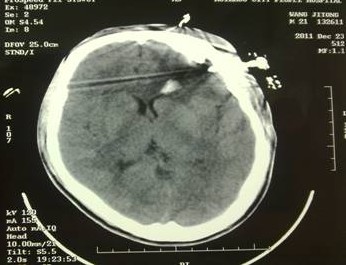

于是家屬慕名求助于我院余永強(qiáng)主任,在傷后第三天轉(zhuǎn)來我院。余永強(qiáng)主任主持術(shù)前討論,決定為患者施行微創(chuàng)手術(shù)清除血腫。通過CT掃描進(jìn)行術(shù)前精確定位,隨后在局麻下進(jìn)行微創(chuàng)手術(shù)。術(shù)中利用余主任設(shè)計(jì)研制的“e形微創(chuàng)手術(shù)定向儀”作引導(dǎo),將穿刺針準(zhǔn)確無誤置入血腫靶心,順利地清除了絕大部分血腫。術(shù)后復(fù)查頭顱CT,血腫清除超過90%(圖2)。憑借微創(chuàng)技術(shù),頭皮僅僅只需要一個(gè)直徑3毫米的小孔,通過一根高科技微創(chuàng)穿刺針,便可達(dá)到同樣的甚至更好的治療效果(圖3)。術(shù)后留置引流1天,第7天即痊愈出院。手術(shù)達(dá)到近乎“完美”的效果!患者親屬大為感慨微創(chuàng)手術(shù)的“神奇”,術(shù)后專程送來錦旗一幅――“微創(chuàng)手術(shù)顯神功” ?。▓D4)

圖2(1):術(shù)后立即復(fù)查CT,血腫清除90%以上,穿刺針定位精確,

無損傷出血;